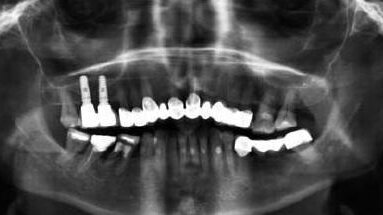

Badaniem klinicznym i radiologicznym stwierdzono odpowiednią szerokość wyrostka zębodołowego do wprowadzenia implantów (Ryc.1 i Ryc.2). Wysokość kości w miejscu implantacji wynosiła od 4-6 mm (Ryc.3). Warunki miejscowe i ogólny stan zdrowia nie stanowiły przeszkody do wykonania zabiegu chirurgicznego obejmującego augmentację dna zatoki szczękowej z dostępu bocznego (otwarty sinus lift) wraz z jednoczasowym wprowadzeniem dwóch implantów.

Gojenie przebiegało bez powikłań. Stan radiologiczny 5 miesięcy po zabiegu przedstawia rycina 13. Z uwagi na widoczne ślady tworzenia się nowej kości w 6-tym miesiącu po zabiegu zdecydowano się na odsłonięcie implantów i wykonanie ostatecznego uzupełnienia protetycznego w postaci zblokowanych koron metalowo-ceramicznych. Zmierzone na tym etapie leczenia wartości stabilizacji implantów wynosiły w obu przypadkach 73 ISQ. Ryciny 14 i 15 przedstawiają stan radiologiczny 2 miesiące po obciążeniu implantów. Na zdjęciu małoobrazkowym zwraca uwagę bardzo wyraźne beleczkowanie kostne.